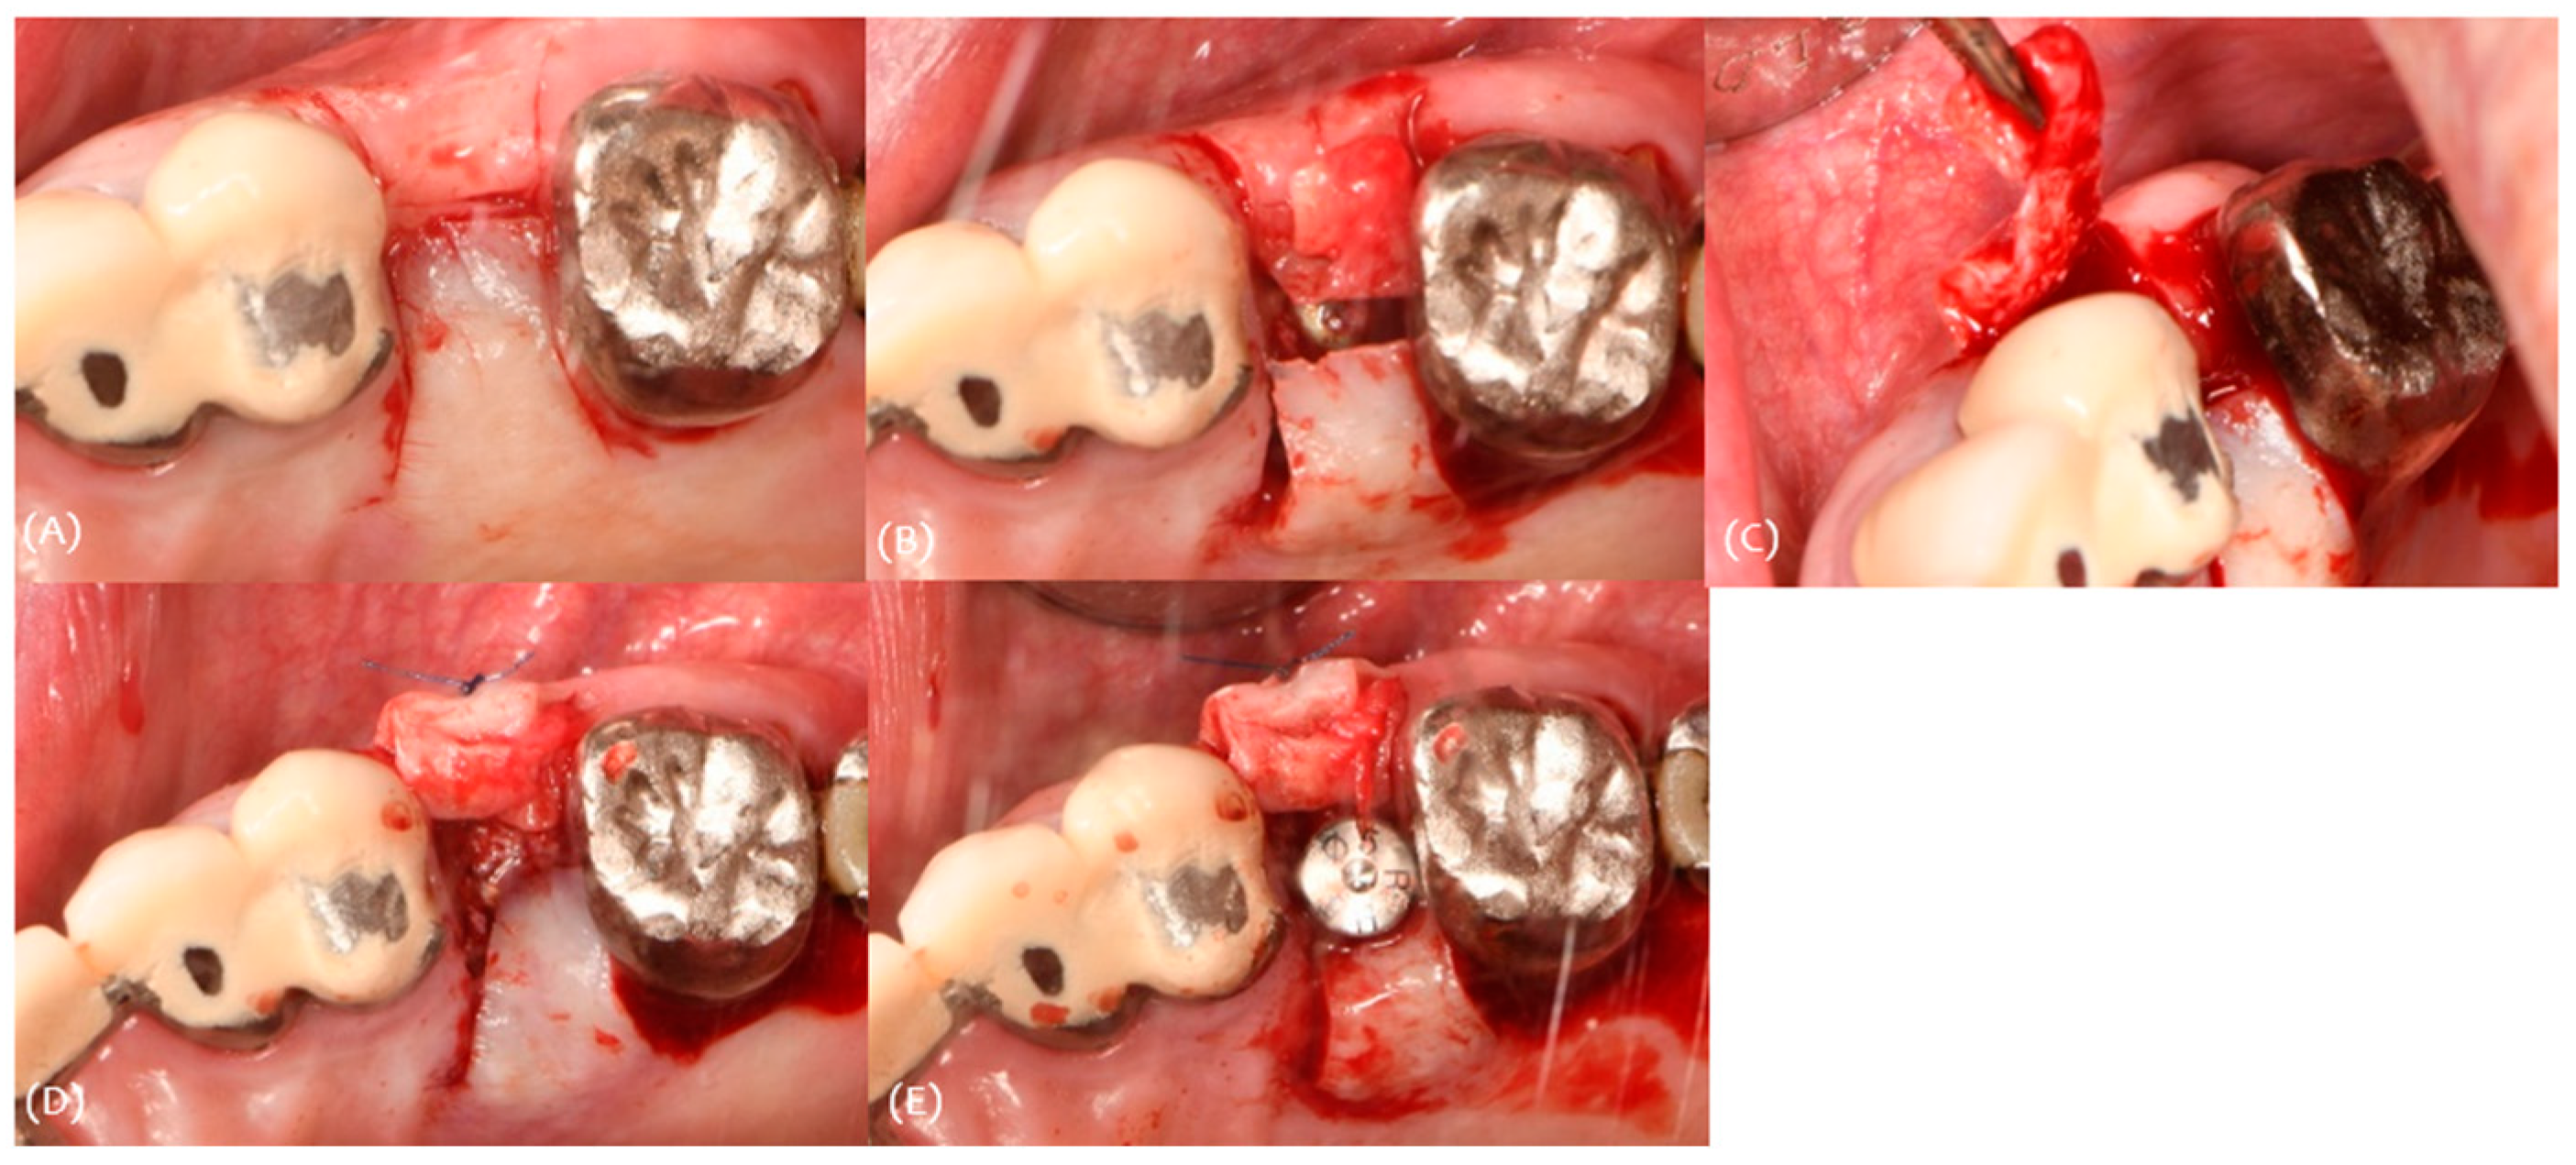

3.3. Case 3

| #25i | #26 | #27 | |

|---|---|---|---|

| Classification (Seibert) | Class I | Class I | |

| Amount of maximum concavity (mm) | 1.2 | 0.8 | |

| Buccal pocket depth (mm) | 222 | ||

| Palatal pocket depth (mm) | 222 | ||

| Bleeding on probing | - | ||

| Gingival recession (mm) | 001 | ||

| Keratinized tissue Width (mm) | 5 | 5 | 6 |

| Site | Pre-Op Concavity (mm) | Increased Buccal Soft Tissue Volume 2 Weeks After Op (mm) | Increased Buccal Soft Tissue Volume 4 Months After Op (mm) | |||

|---|---|---|---|---|---|---|

| #26i | #27i | #26i | #27i | #26i | #27i | |

| Distal | 0.8 | 0.4 | Δ 0.913 | Δ 1.43 | Δ 0.983 | Δ 0.52 |

| Disto-middle | 0.9 | 0.6 | Δ 1.22 | Δ 1.47 | Δ 0.695 | Δ 0.54 |

| Middle | 1.2 | 0.8 | Δ 1.18 | Δ 1.59 | Δ 1.01 | Δ 0.606 |

| Mesio-middle | 1 | 0.7 | Δ 1.4 | Δ 1.5 | Δ 1.03 | Δ 0.226 |

| Msesial | 0.8 | 0.5 | Δ 1.45 | Δ 1.34 | Δ 0.358 | Δ 0.467 |

| Average | 0.94 | 0.6 | Δ 1.2326 | Δ 1.466 | Δ 0.8152 | Δ 0.4718 |